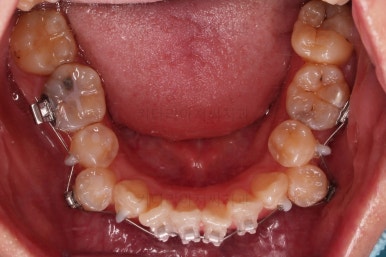

초진 시 입안의 모습입니다.

이미 썩어서 부러진 치아도 몇 개 보이고요.

많이 삐뚤어진 치아쪽은 양치가 힘들어 이미 많이 썩어 있는 상태에 덧니쪽은 잇몸도 많이 내려간 상태였습니다.

아랫니는 많이 삐뚤긴 했지만 옆라인, 턱의 크기 등 모든 걸 종합적으로 판단해 비발치로 진행하기로 했습니다.